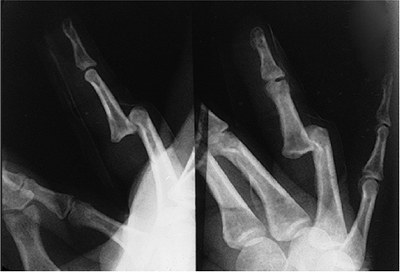

Figure 10-4 X-ray appearance of a dorsal PIP joint dislocation. -

In the unreduced state, these radiographs

dorsal neck of the proximal phalanx (Figure 10-4). -

![]() |

Figure 10-5 X-ray appearance of a lateral dislocation of the PIP joint.

dislocation. It involves disruption of the origin or insertion of the

collateral ligament, disruption of the interval between the proper

collateral ligament and the accessory collateral ligament, and partial

disruption of the palmar plate attachment.

Complete lateral dislocations are clinically apparent, but subluxations may not be as obvious because of swelling.

Stress testing of the collateral ligament and accessory stabilizers is performed with the PIP joint in full extension.

An angular deformity of 20 degrees or more on the stress test is diagnostic of significant instability.